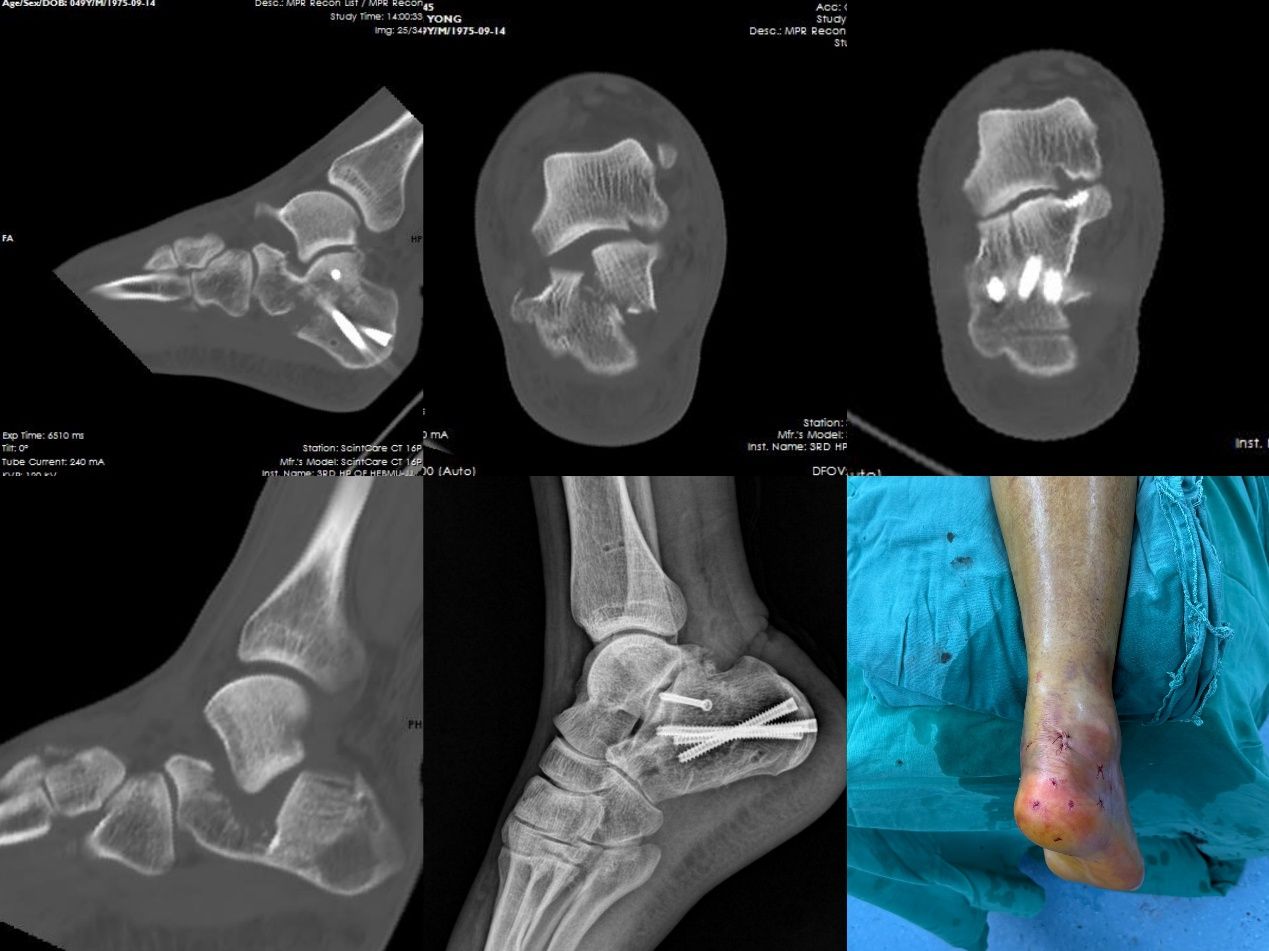

该项微创手术具有多项显著优点。首先,手术无需传统大切口。医生仅通过体表几个如“钥匙孔”般的微小穿刺点,借助特殊器械与术中实时影像引导,在闭合状态下实现骨折块的精准对位,恢复跟骨原有结构。复位后采用经皮植入螺钉完成固定,最大限度保留软组织完整性,使患者可更早开展康复训练。

其次,该手术可降低软组织损伤及相关并发症。手术过程中对肌肉、韧带、血管及神经的影响较小,从而显著减少术后感染、皮肤坏死、伤口愈合不良等常见风险。患者不再需要为并发症过度担忧,康复过程更加顺畅安心。

不仅如此,由于手术创伤小,患者术后疼痛感也明显减轻,可以更早开始踝关节功能锻炼与系统康复。“早活动”是促进骨折愈合、避免关节僵硬、提升功能恢复效果的关键。微创手术让患者能更快、更主动地投入康复训练,整体恢复周期大幅缩短,回归日常生活的速度也明显加快。